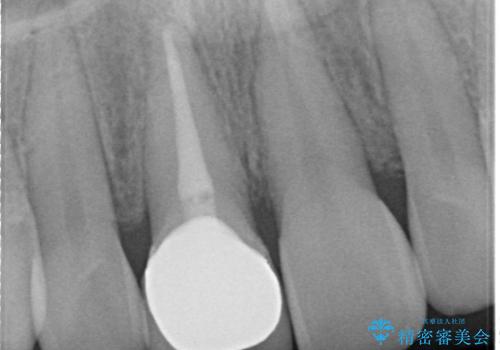

上顎前歯は根管治療後にオールセラミッククラウン(エクセレント)で修復を行なっております。